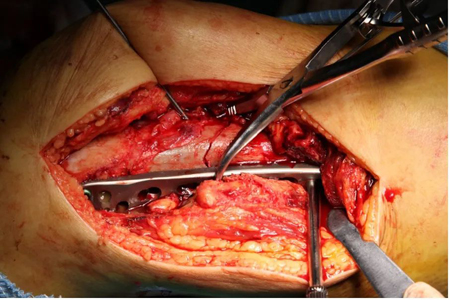

吴新宝团队术前详细规划,反复推演手术流程。2021年9月27日,在短短不到1小时的时间内,手术团队按照手术设计顺利完成了骨折的复位固定。术中影像显示,骨折解剖复位,定制钢板位置得当,螺钉位置理想,完美实现了术前规划的手术目标。